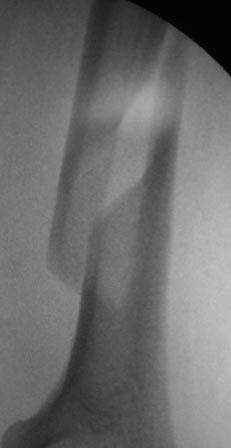

Операция 16.03.17г. БИОС закрытым способом СhM под ЭОП.В ходе рассверливания к/м канала дистального отломка, видимо, имеющийся осколок откололся , но стояние было удовлетворительное, в конце операции при контрольной проверке под ЭОП все было нормально (см.снимки под ЭОП).

На контрольной Р-грамме на следующий день – осколок сместился. Коллеги рекомендуют или щилом втолкнуть, или маленьким разрезом открыть и репонировать, и т.д.

по поводу "противных рентгенологов"))... на снимках ЭОП и R-грамм разница в проекциях градусов 30!..Ну , а если осколок так легко "гуляет",то плечо навряд ли простит такое,не?